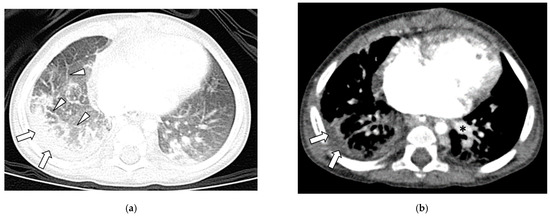

3.3. Lung Findings

3.4. Airway Findings

| TOL | 0/49 (0%) | 43/54 (80%) | <0.001 |

| Bronchial Wall Thickening | 0/49 (0%) | 33/54 (61%) | <0.001 |

| Bronchiectasis | 0/49 (0%) | 30/54 (56%) | <0.001 |